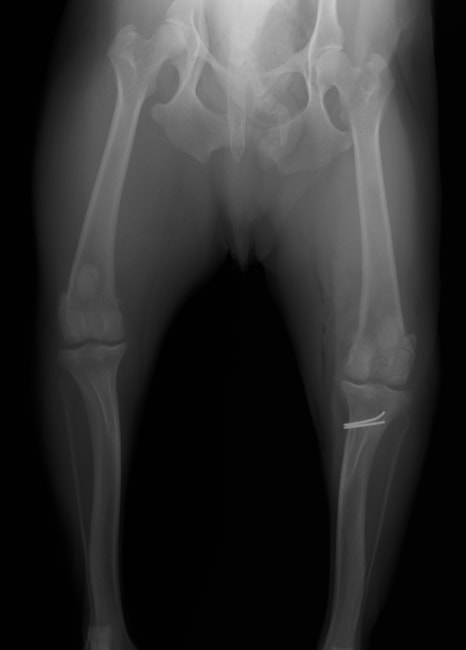

■ 症例24 キャバリア 7か月

左右膝蓋骨内方脱臼(左:グレードⅣ 右:グレードⅢ)

以前から左右後肢の跛行が認められ、整形外科学的検査・レントゲン検査により左右の膝蓋骨脱臼が認められた。症状が重度である左膝の膝蓋骨脱臼整復術を行った。外科手技は縫工筋及び内側広筋の解放、脛骨粗面の外側転位、滑車ブロック形造溝術、内外側関節方の縫縮を実施した。術後一か月時点で、左の膝蓋骨は安定しており経過は良好である。

本症例は成長期における重度の膝蓋骨脱臼であり、術後の再発の可能性もあるため、経過をしっかりと観察していく必要がある。また、今回手術を実施していない右膝に関しても経過を観察し、手術を検討していくこととする。